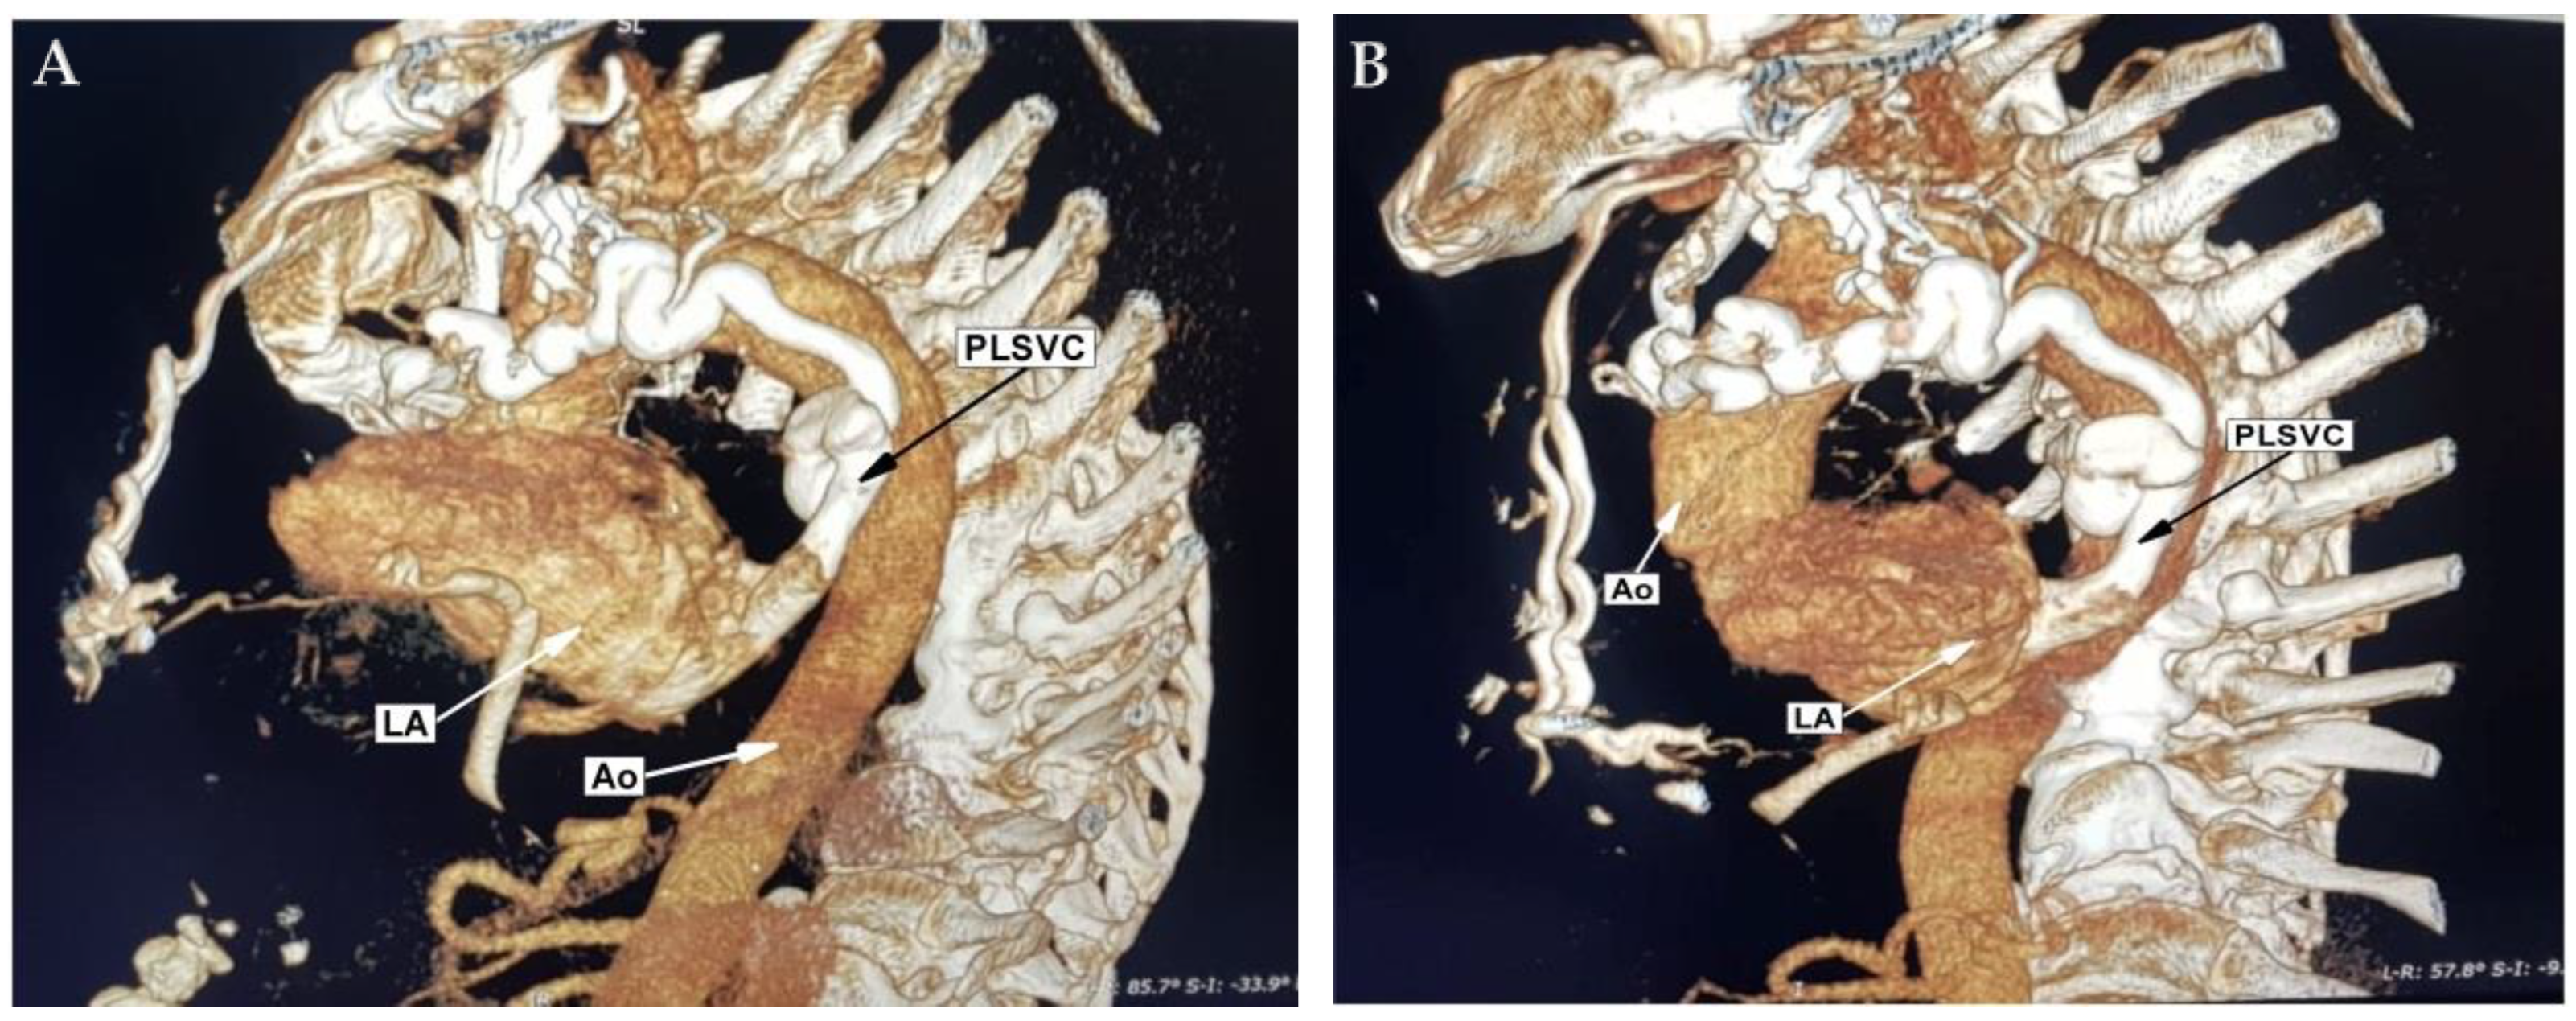

2. Case Report